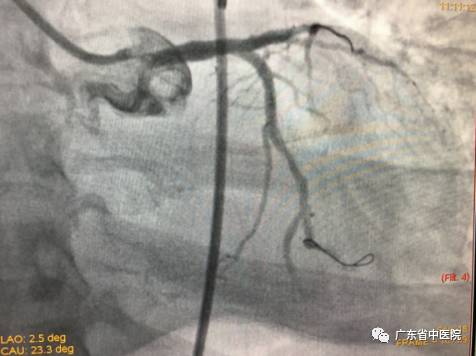

当冠脉造影结果出来后,大家都倒吸了一口冷气:患者是极高危的“左主干”并“前三叉病变”、右冠“慢性完全闭塞病变”。三条冠脉都是重度病变,而且在最重要的冠状动脉左主干末端、前降支开口、回旋支开口都是99%狭窄。稍有不慎,患者随时可能在台上猝死!

造影刚刚结束,患者便又再次出现了室颤。在同家属简单沟通病情后,一场与死神争夺生命的战斗开始了。在IABP辅助下,不到10分钟,旋支支架到位、植入,前降支球囊进行CRUSH操作。正在此时,患者心脏突然停止了跳动!吕主任处乱不惊,马上安排一组人员进行心肺复苏,同时继续操作器械。在体外人工心脏按压的辅助下,成功将最后一枚支架植入,完成血管重建。患者恢复自主心律后,反复出现室速、室颤。这是心肌梗死并发症之一,死亡率极高的“交感电风暴”!团队立即给予电除颤和积极的药物治疗,并派专人24小时守护,以便随时进行心肺复苏。室速、室颤一轮接一轮,经过30余次的除颤、复苏,“风暴”总算过去。病人心律逐渐平稳下来,病情稳定。出院前复查心脏彩超提示左室射血分数已经回升至53%。当病人救治情况反馈回至当地医院后,他们对省中医院的救治水平给予了充分认可和高度赞扬,认为“这样的病人都能救过来,真是厉害!”

分叉病变手术前后造影